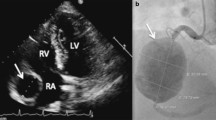

An 11 year-old boy presented to a pediatric hospital with chest and jaw pain while playing one year after a prolonged febrile illness . Initially, CT angiography was performed (A, image courtesy of Dr. Christopher Learn) that showed thrombus in a calcified aneurysm of the left anterior descending coronary artery (LAD, arrow). In the setting of elevation of the serum troponin and possible need for coronary intervention, the patient was transferred to a nearby adult hospital. Invasive angiography (B) showed thrombus nearly occluding LAD that was treated with angioplasty and stent placement. C. Coronary MRA performed in another patient with KD using a navigator-triggered slab prescribed perpendicular to the aortic root demonstrates a 9 mm proximal LAD aneurysm (arrow). LV = left ventricle Ao = aorta.

Arnold et al. compared conventional angiography, multi-detector CT (MDCT) and MRI in 16 patients and showed 100% concordance between conventional angiography and MDCT, and 93% concordance between MRI and coronary angiography for aneurysm detection [59]. MRI missed one stenotic lesion, while providing additional information regarding myocardial inflammation and injury. Kan et al. recently summarized the safety and accuracy of contemporary CT with ultra-low radiation exposure for pediatric patients [60], including 5 with suspected coronary involvement in KD with nondiagnostic CMR examination. More recently, using free-breathing, T2-prepared, 3D-SSFP, whole heart approach with navigator gating and tracking, Greil et al. demonstrated complete and excellent agreement between MRA and coronary angiography [54].

Mavrogeni et al. reported comprehensive CMR findings using both coronary and myocardial evaluation in 13 KD patients thought to be in convalescence (stage II and III, 20–25 days after disease onset) [61]. Of the six patients with demonstrable myocardial inflammation by T2W STIR (which had resolved in all 6 by repeat CMR 3 months later), only three had evident abnormality by LGE yet all had lower LV ejection fraction by cine imaging. Additional 3D ECG-gated steady state free precession navigator-gated non-contrast coronary MRA identified coronary aneurysms and intracoronary thrombus, some of which were missed by echocardiography. In joint guidelines issued by the American Academy of Pediatrics and the American Heart Association in 2004, echocardiography, MRI, and conventional coronary angiography were all accorded level of evidence C for detection of coronary abnormalities due to lack of prospective data [62].